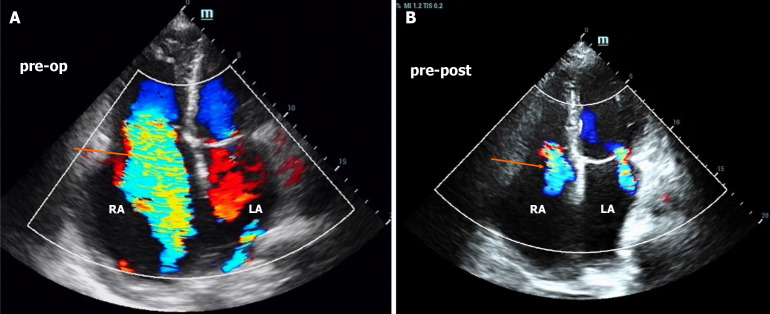

Case summary: A 57-year-old man was admitted to the hospital with complaints of exertional dyspnea for more than 10 years. Physical examination revealed wet crackles in the lungs and a continuous machinery murmur in the left lower back and groin area. Asymmetric edema and varicose veins were observed in the lower limbs. Echocardiography revealed a dilated right ventricle with severe pulmonary hypertension. Computed tomography revealed a left common iliac arteriovenous fistula linked to prior lumbar disc surgery. Surgical repair resolved the symptoms, with echocardiography at 4 months showing a reduced right atrium (RA) and ventricular (RV) diameter and tricuspid regurgitation. However, during the 2-year follow-up, gradual RA and RV re-expansion (from 35 mm to 51 mm and from 26 mm to 46 mm, respectively) was observed, despite sustained clinical stability.